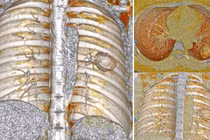

Chụp MRI toàn thân giúp phát hiện sớm ung thư - Ảnh minh họa BVCC

MRI DWIBS là kỹ thuật chụp cộng hưởng từ khuếch tán toàn thân xóa nền, cho phép tầm soát toàn bộ cơ thể trong một lần chụp.

Phương pháp này được ứng dụng hiệu quả trong tầm soát ung thư, phát hiện di căn và theo dõi tiến triển bệnh. So với các phương pháp chẩn đoán hình ảnh khác, MRI DWIBS sở hữu nhiều ưu điểm như: không nhiễm xạ, không cần tiêm thuốc cản quang, thời gian chụp toàn thân rất kỹ từ 50 đến 60 phút, người bệnh có thể sinh hoạt bình thường ngay sau khi thực hiện và phù hợp với cả người mắc bệnh đái tháo đường.